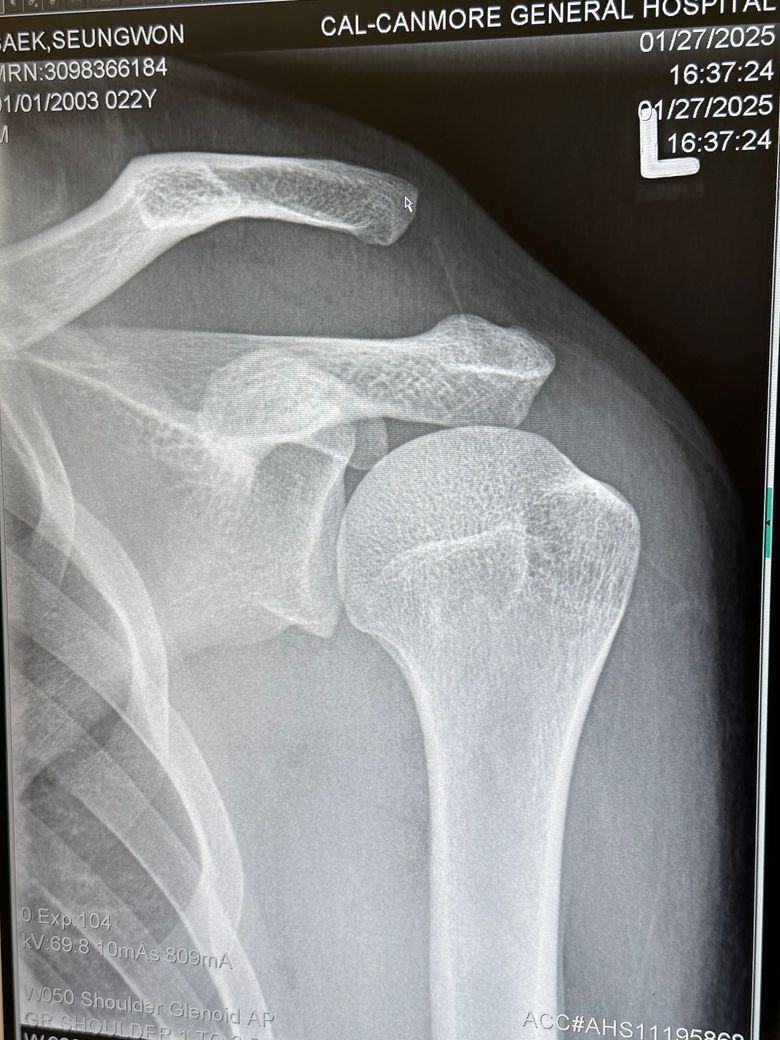

어깨 이거 문제 없이 괜찮은건가요??

캐나다에서 스키타다 심하게 넘어졌습니다 어깨가 안 움직이길래 바로 병원으로 왔고 익스레이도 촬영했습니다 여기 캐나다 병원에서는 문제가 없고 붕대로 감고 있으면 된다고 하면서 설명하기를 나라마다 치료하는 게 다르므로 한국 병원에 다시 가보라고 합니다 아직 여행 일정이 남아 다음주 귀국 예정인데 캐나다 의사선생님 말대로 그냥 붕대만 해도 문제가 없을까요? 캐나다 의사선생님을 믿지 못하는 것이 아니라 한국에서 치료를 받지 못하고 있자니 제 마음이 불안해서 확실하게 알고 싶습니다

• 2번 째 사진

지금 어깨 관절의 뼈 정렬이 좋지 않스니다. 엑스레이 상 보시면 쇄골과 견갑골이 서로 간격이 많이 벌어져있습니다. AC JOINT 라고 해서 쇄골과 견갈골 견봉과의 간격이 너무 벌어져있습니다. 그쪽 인대가 늘어났던지 아니면 삼각근이나 어깨 안정화 시켜주는 근육이 손상을 입은것으로 보입니다. 저런 경우에는 디테일하게 초음파 촬영을 해서 인대에 문제인지 아니면 힘줄에 문제인지를 보고 그에 따른 약물치료나 주사치료를 하면 좋겠지만, 현재 병원에서 하실 수 있는게 고정(붕대)이시면 어깨뼈를 최대한 안정적으로 고정해주시는게 지금 상황에서는 현명한 대처법으로 보입니다. 스키타다가 넘어지면서 AC JOINT라는 관절의 문제가 생긴것으로 보이는데, 일단 인대가 파열이나 끊어진게 아니면 고정 방법으로 해서 연부조직의 자가적인 회복을 기대해볼 수도 있습니다. 우선은 그렇게 해주시는게 좋을거 같습니다.